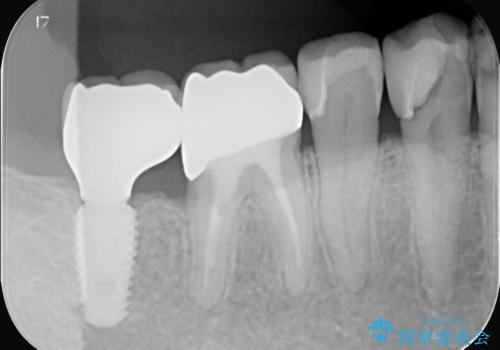

- 治療計画

- 患者様は、右側の奥歯でしっかり噛めないことを主訴に来院されました。診察の結果、右上6・右下6の根管治療が不十分で、感染のリスクがある状態と判断。これらの歯は再根管治療を行い、セラミッククラウンで補綴することにしました。また、右上7・右下7は欠損しており、噛み合わせを回復するためにインプラント治療を計画しました。

まず、右上6・右下6の根管治療を再度行い、根の状態をしっかり整えた上で、セラミッククラウンを装着しました。さらに、欠損していた右上7・右下7にはインプラントを埋入し、セラミッククラウンを装着。治療後は、「奥歯でしっかり噛めるようになり、不安なく食事ができるようになった」と患者様にも大変ご満足いただきました。